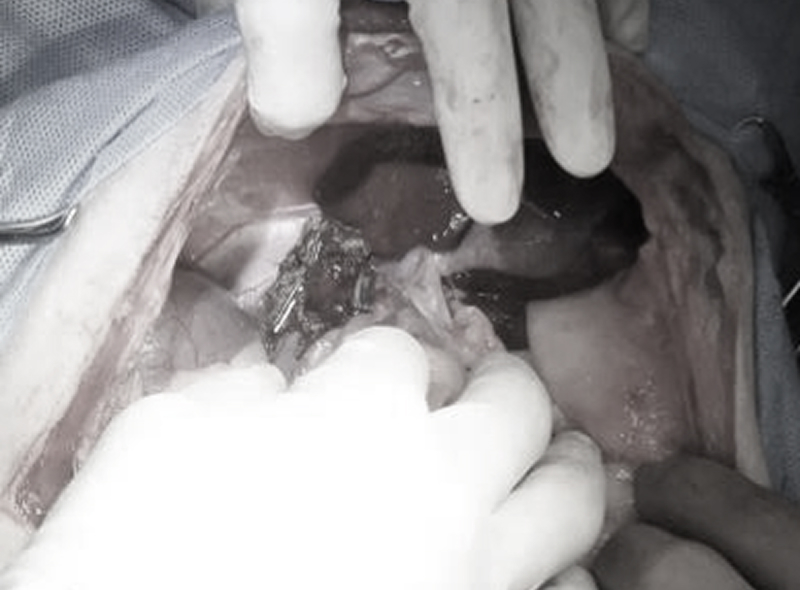

当院では舌や下顎に発生した扁平上皮癌に対して、完全切除を行うために舌下顎全切除術を実施しております。この術式は実施可能な施設が少ないと考えられ、一般的な術式ではありません。しかし、当院には年単位の長期生存が得られている患者様がいます。

治療にはメリット・デメリットがあります。治療を検討される方はご相談ください。